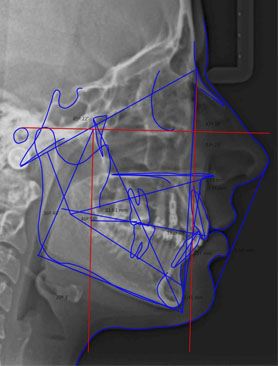

ESTUDIOS RADIOGRÁFICOS

Contamos con especialistas en Radiología Oral y Maxilofacial, para dar certeza en la calidad de nuestros estudios y diagnósticos.

Nuestros estudios radiográficos son todos digitales, con ello hemos eliminado el proceso de revelado, cuyos líquidos son contaminantes del medio ambiente al ser equipos digitales, utilizan un sensor que disminuye las dosis necesarias de rayos X, protegiendo y reduciendo el riesgo de exposición a la radiación.

Somos un grupo de Radiología e imagenología del área Maxilofacial, dedicados a la realización de estudios diagnósticos para el cirujano dentista y especialista de cabeza y cuello.

Brindar estudios diagnósticos en el área Maxilofacial de la más alta calidad para nuestros pacientes.